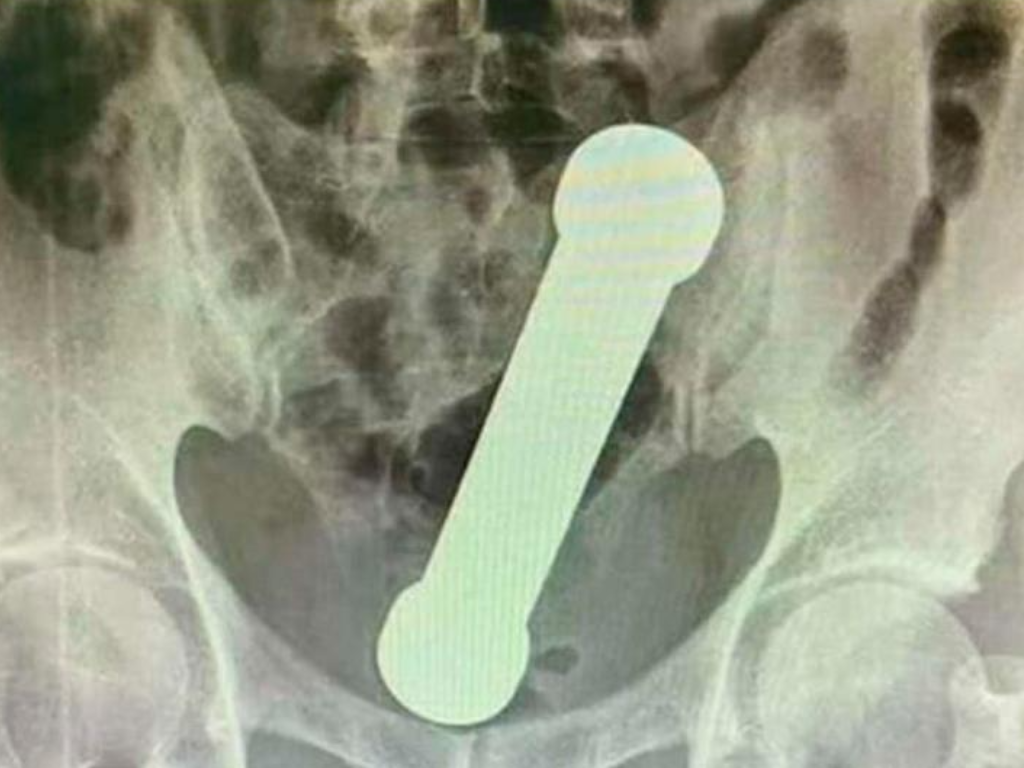

La víctima, de 54 años, se presentó en un hospital de la ciudad Manaos, noroeste de Brasil, con dolor abdominal, náuseas y dificultad para defecar. Le hicieron una radiografía que mostró que tenía un objeto de metal de 4,4 libras y casi 20 cm en el ano. Se calcula que la mancuerna estuvo alojada allí por lo menos dos días.

En primera instancia, los cirujanos intentaron extraerle el objeto usando pinzas, pero finalmente tuvieron que intervenirlo. La operación fue exitosa y fue dado de alta después de tres días sin complicaciones.